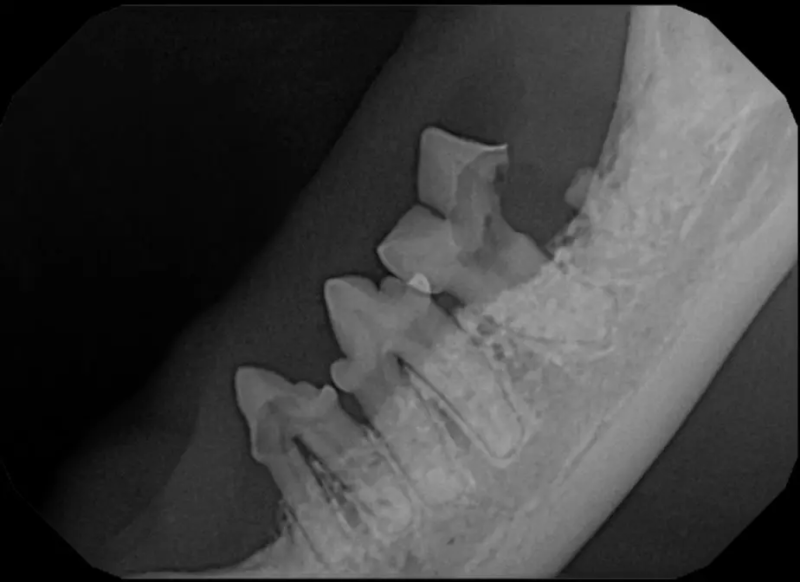

Root canal therapy is an excellent option for saving important teeth that have been fractured or are determined to be non-vital. The procedure is performed exactly as it would be for a human, except your pet will be dreaming peacefully under anesthesia. In many cases, root canal therapy is much easier on your pet than extraction, and preserves the structure of the tooth. It is important to have the root canal x-rayed periodically to monitor for any problems.